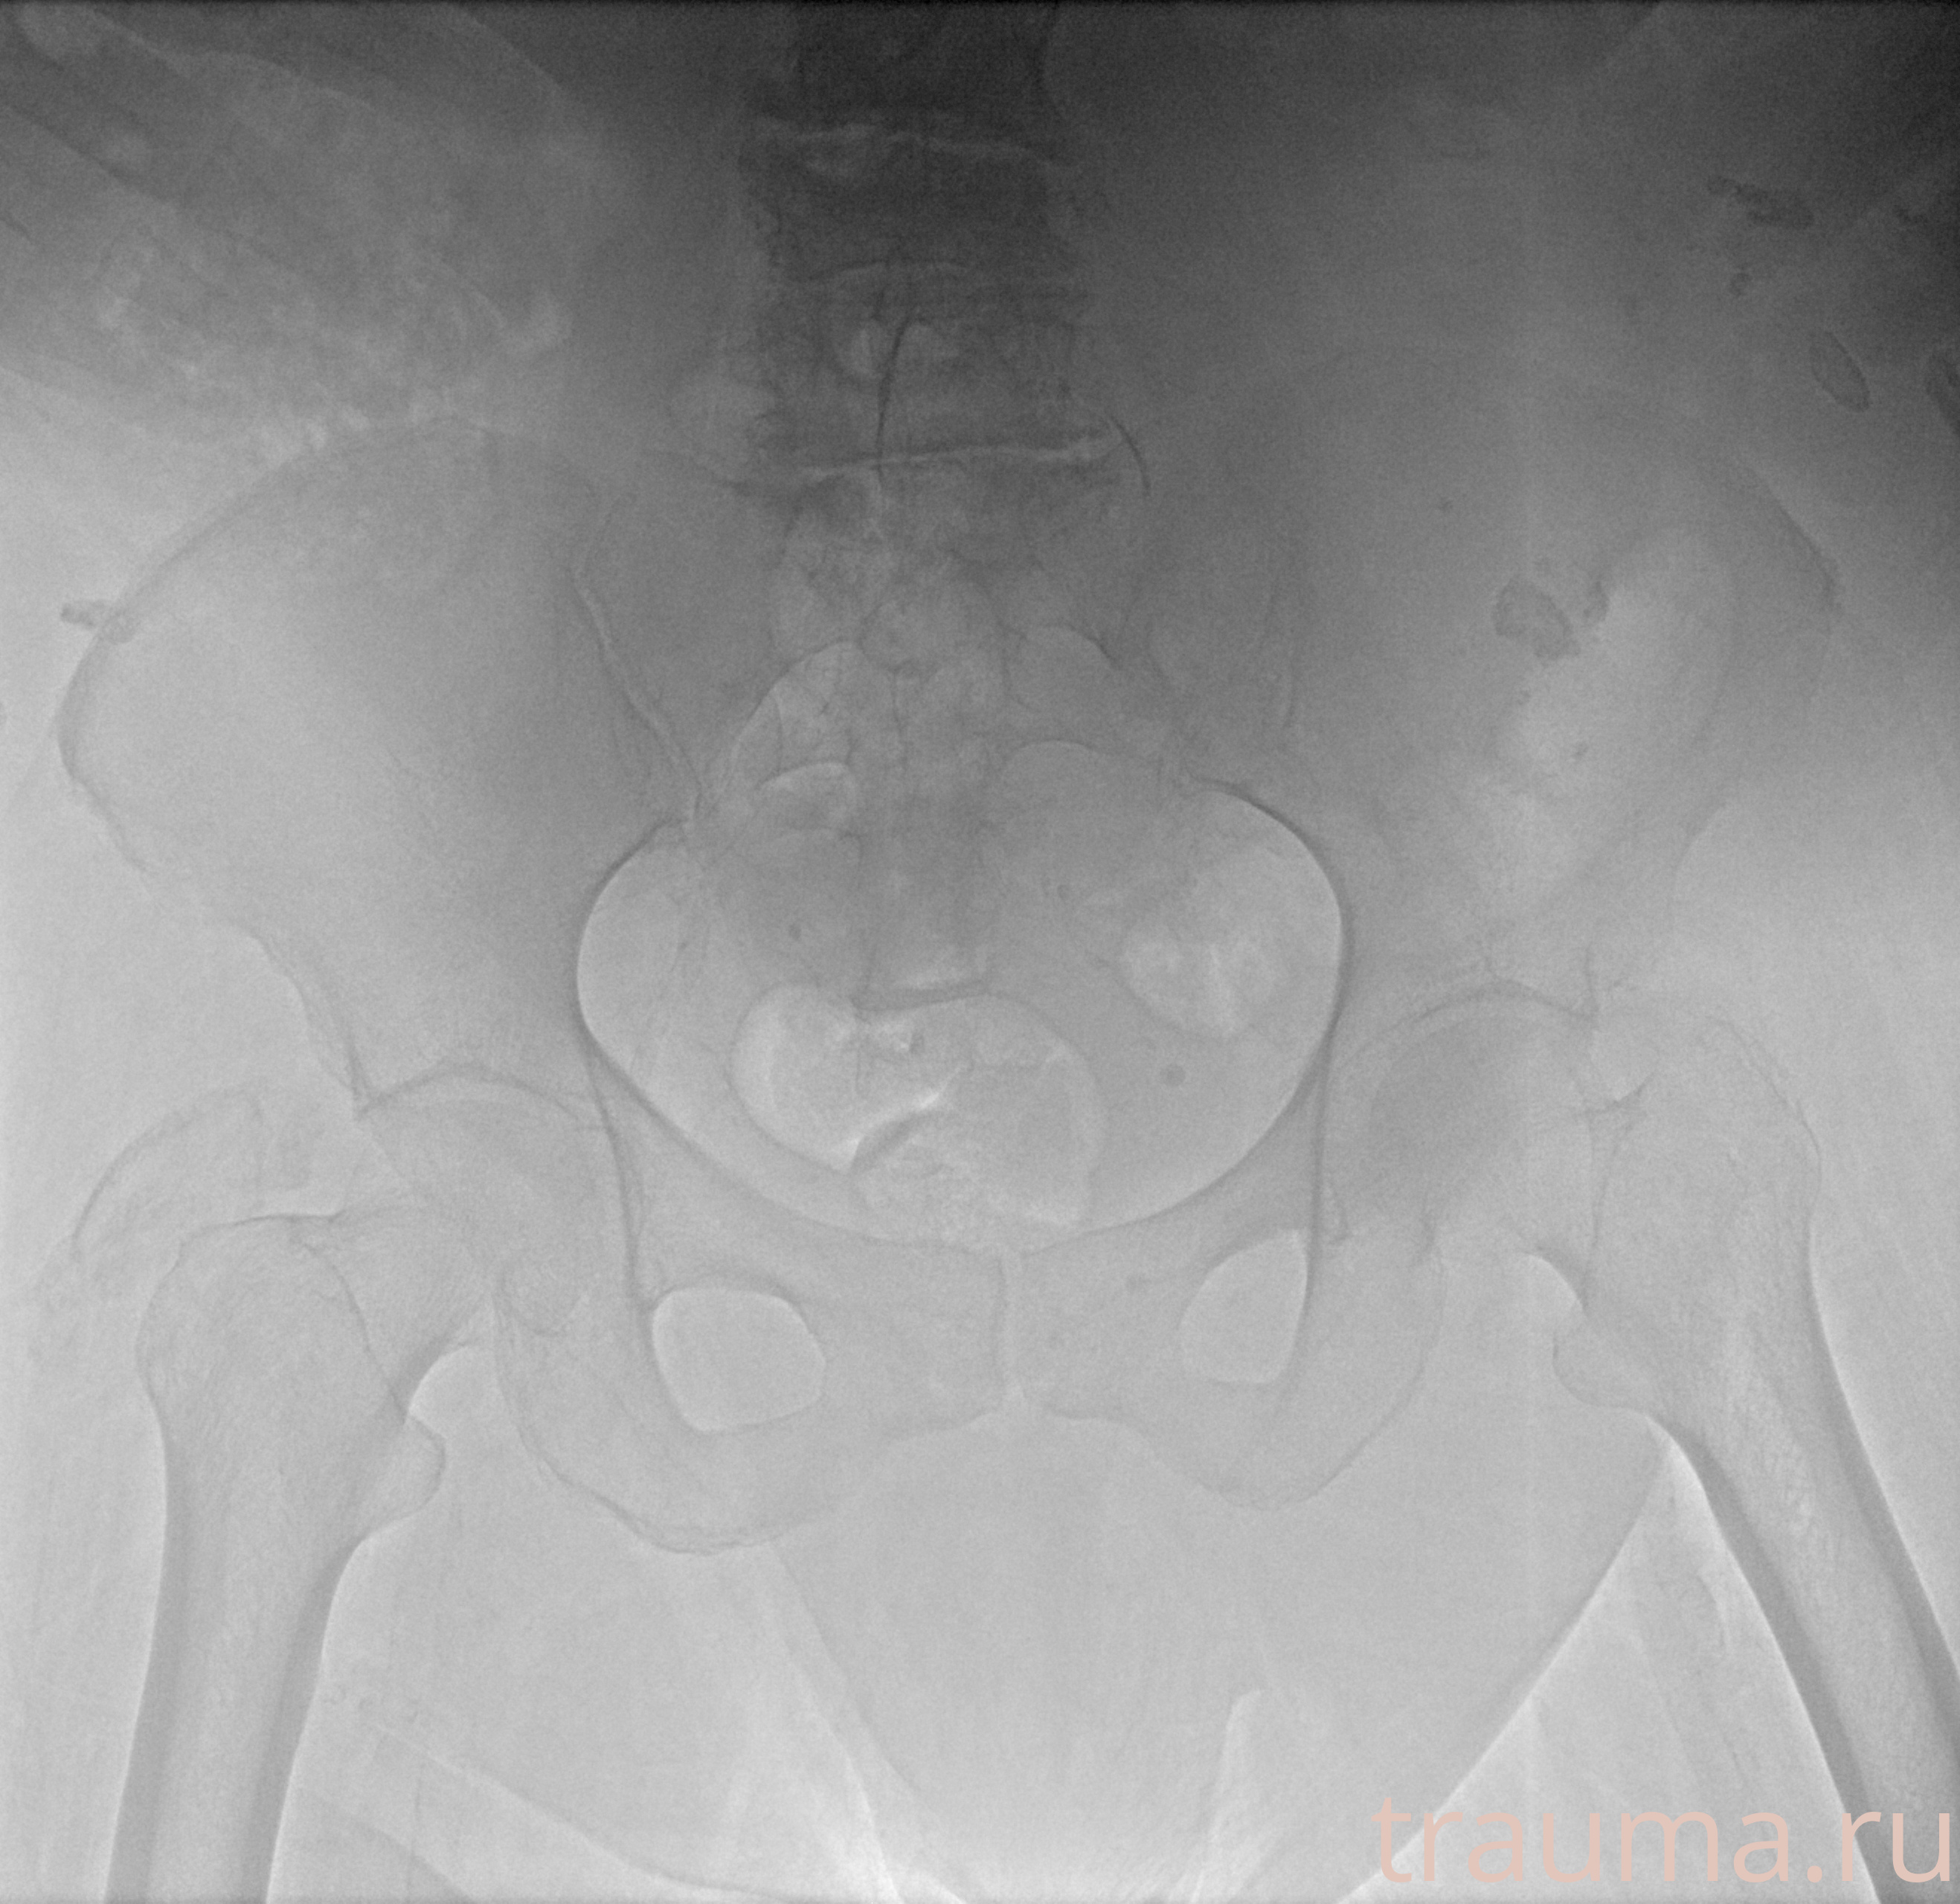

Рентген на дому: по вашему адресу приезжает врач-рентгенолог, травматолог-ортопед с мобильным рентгеновским аппаратом, проводит диагностику травмы или заболевания, делает необходимые рентгенограммы, дает рекомендации по дальнейшему лечению. Получить качественные снимки в домашних условиях возможно благодаря уникальной методике, разработанной МосРентген Центром для института  Склифосовского